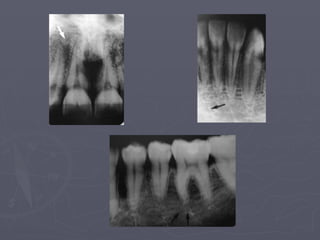

Cervical Burnout

► It is a diffuse radiolucent

areas with ill-defined

borders on the mesial or

distal aspects of teeth in

the cervical region

between the enamel cap

and the crest of the

alveolar ridge.

► It is not to be confused

Nutrient canals :

The arrows above

identify nutrient

Canals.

They are most often seen

in

Persons with thin bone

and in

Those with high blood

pressure

Or advanced

periodontitis.

Nutrient canals